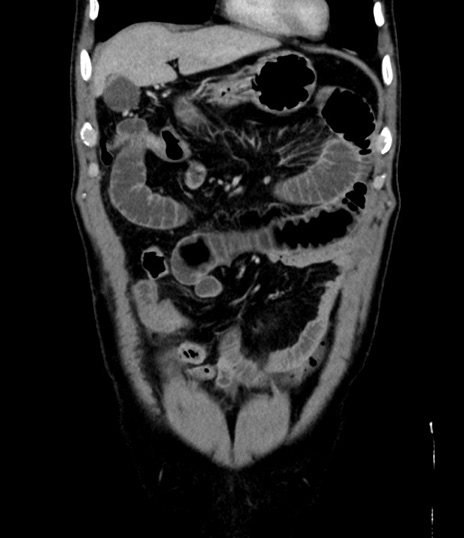

症例8(冠状断像)

【症例】 60歳代男性

【主訴】 黒色吐物

【現病歴】 4日前から嘔気自覚、2日前の朝食後にも嘔気あり、自分で手で嘔吐反射起こし嘔吐したところ血が混ざっていたため受診。

【既往歴】 5年前汎発性腹膜炎を伴う急性虫垂炎で手術、高血圧、前立腺肥大症、高脂血症

【身体所見】 腹部正中に手術癩痕あり 腹部平坦・軟圧痛なし膨満感あり

【データ】WBC 8400、CRP 4.54